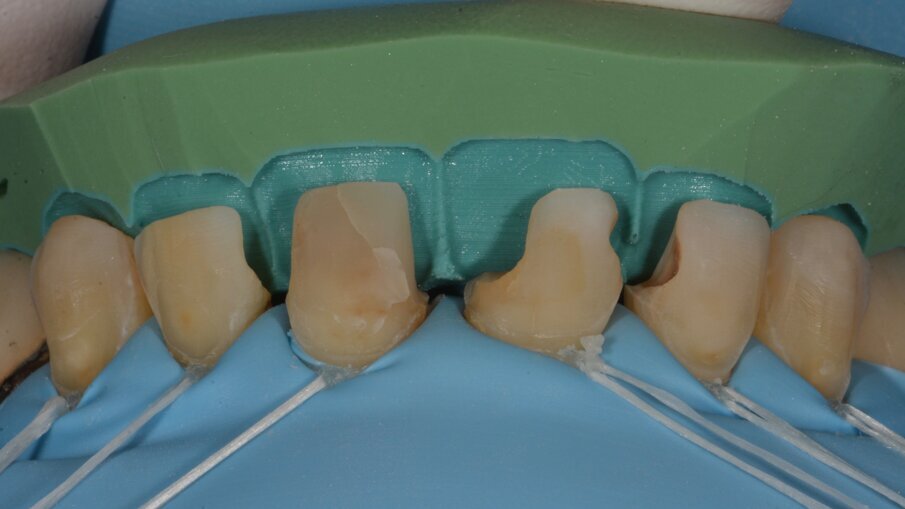

Aan de hand van het digitale model werd een palatale putty gemaakt, die dienst deed als basis van onze nieuwe opbouw.

Eerst wordt een dunne laag 3M Filtek Universal Restorative aangebracht op de putty en uitgestreken met een kwastje om de kans op luchtbellen te verkleinen.

Het resultaat na voorzichtig wegnemen van de palatale putty.